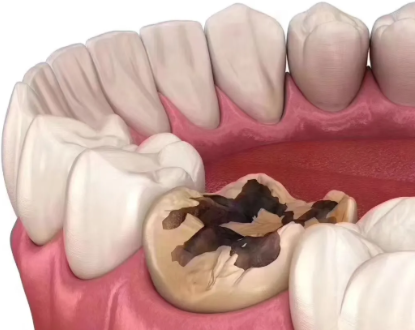

蛀牙属于牙体硬组织的慢性疾病,主要是细菌侵蚀牙釉质、牙本质导致的缺损,治疗核心是修复缺损、终止病变,这类诊疗属于口腔内科范畴。在综合医院里,大多没有过于细分的口腔科室,直接挂口腔科就能完成补牙诊疗,医生会先检查蛀牙的重度程度,判断是直接补牙还是需要根管治疗等后续处理。

在大型口腔专科医院,科室划分更精细化,会把口腔疾病分为牙体牙髓科、牙周科、口腔外科等,此时蛀牙补牙就可以挂牙体牙髓科,这个科室专门处理牙体硬组织和牙髓的疾病,医生在蛀牙诊断、补牙材料选择、复杂蛀牙处理(比如深龋接近牙髓、牙髓炎前期)上更有针对性,诊疗流程也会更专精。需要明确的是,蛀牙补牙不需要挂口腔外科,因为口腔外科主要负责拔牙、口腔颌面手术、智齿拔除等有创手术类项目,补牙属于修复和保守治疗,和外科范畴无关。